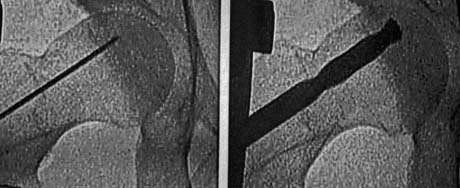

Under C-arm the special drill is inserted in the femoral head and remove osseous part of the core for the decompression

Under fluoroscopic control carried out targeting the defect – aseptic necrosis of femoral head right

Opening bone tunnel to the point of osteonecrosis of the femoral head